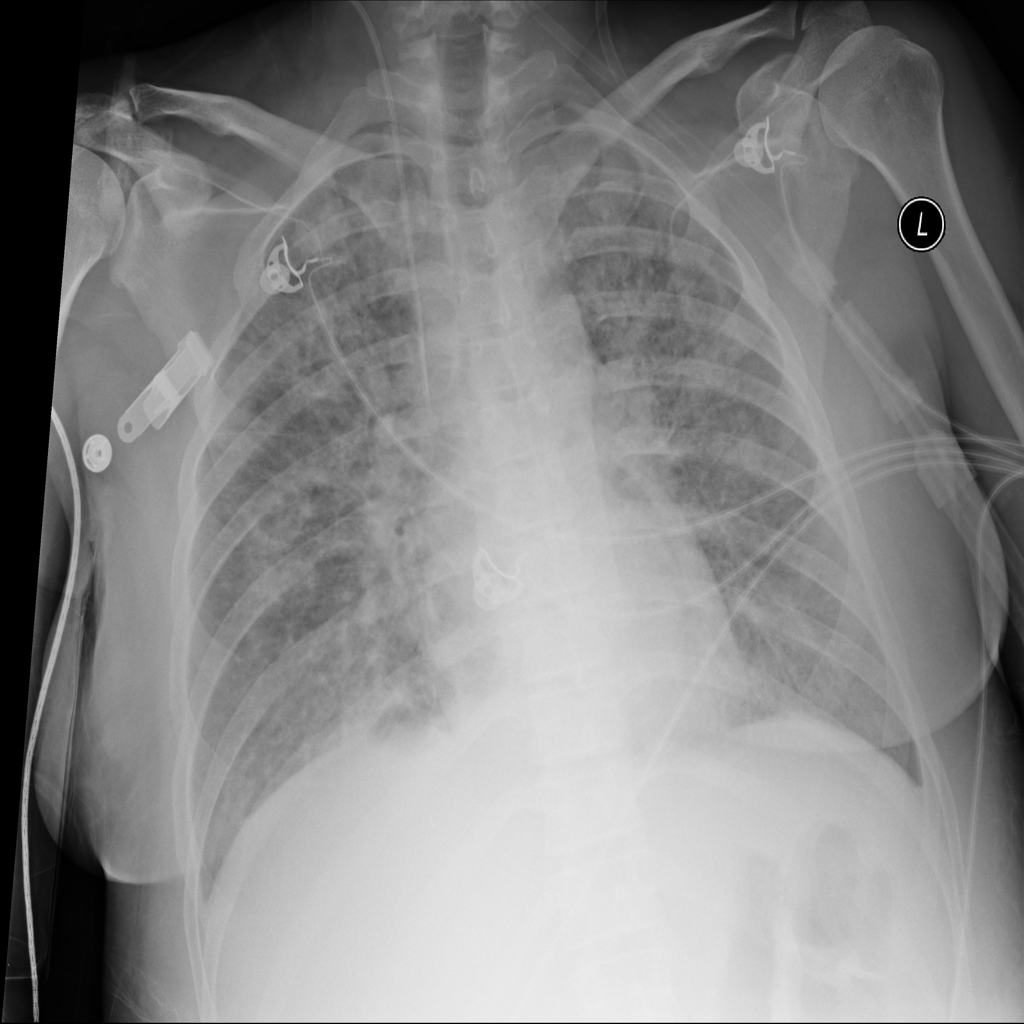

PAT-E828 · IMG-005Edema

PAT-E828 · IMG-005

AP